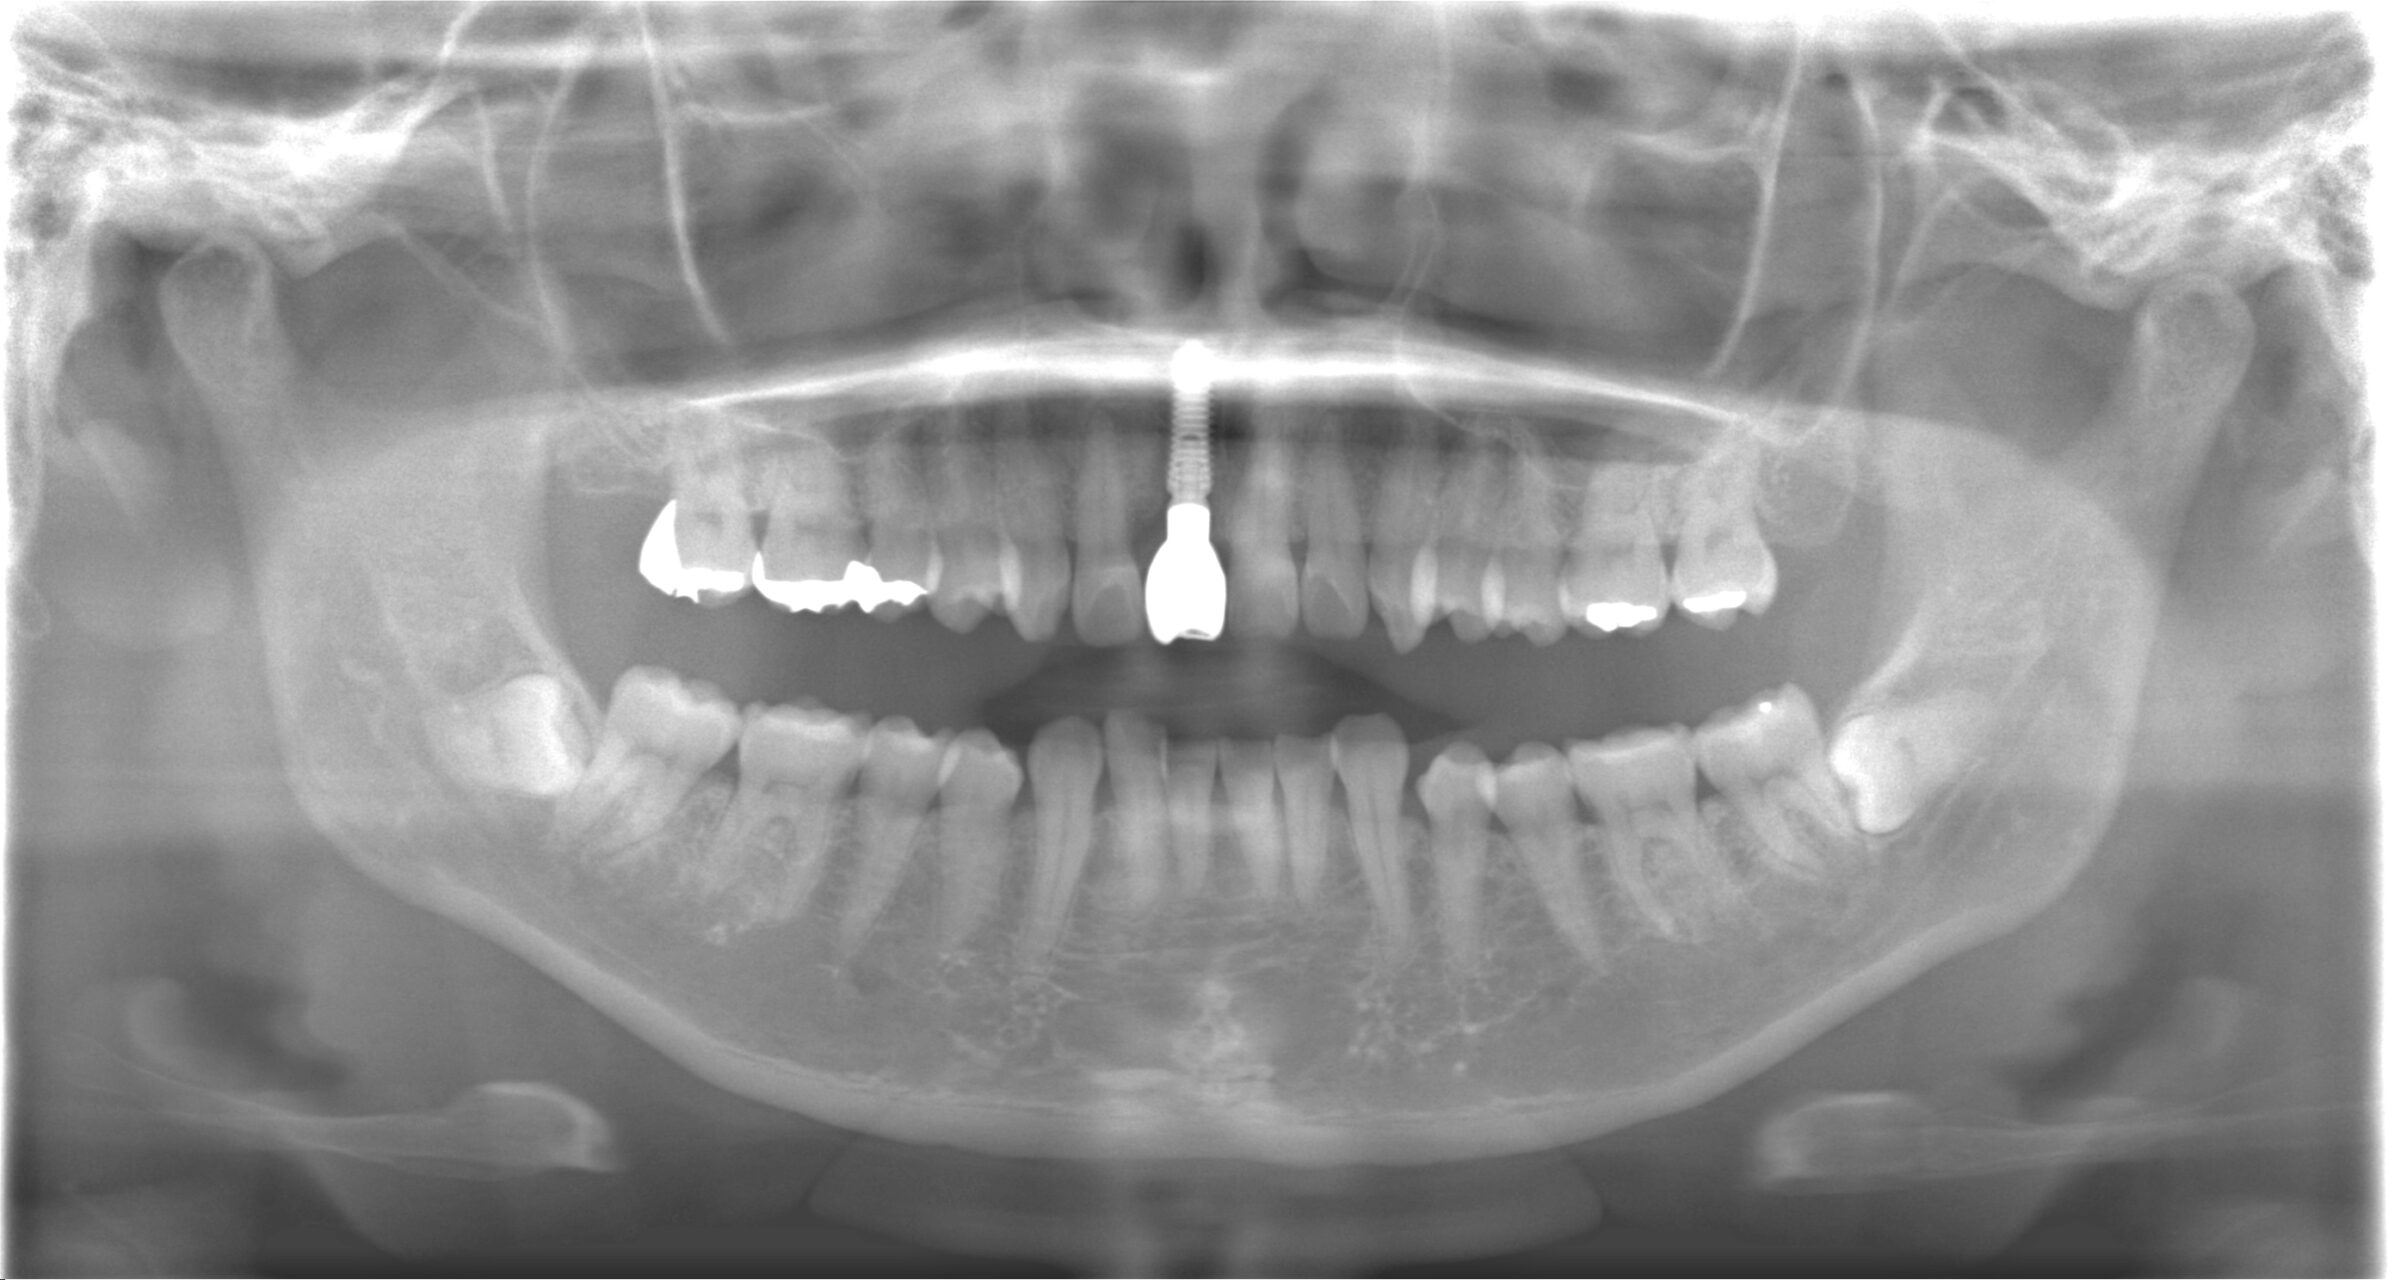

治療後のレントゲン写真